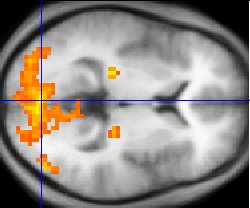

Functional magnetic resonance imaging (fMRI), is the medical imaging technique used to measure the haemodynamic response of the brain in relation to the neural activities.[12] It is one of the most commonly used devices to measure brain functions and is relatively inexpensive to perform in a clinical setting. The onset of neural activity leads to a systematic series of physiological changes in the local network of blood vessels that include changes in the cerebral blood volume per unit of brain tissue (CBV), changes in the rate of cerebral blood flow, and changes in the concentration of oxyhemoglobin and deoxyhemoglobin. There are different fMRI techniques that can pick up a functional signal corresponding to changes in each of the previously mentioned components of the haemodynamic response. The most common functional imaging signal is the blood-oxygen-level dependent signal (BOLD), which primarily corresponds to the concentration of deoxyhemoglobin.[13] The BOLD effect is based on the fact that when neuronal activity is increased in one part of the brain, there is also an increased amount of cerebral blood flow to that area which is the basis of haemodynamic response. This increase in blood flow produces an increase in the ratio of oxygenated hemoglobin relative to deoxygenated hemoglobin in that specific area. The difference in magnetic properties of oxygenated and deoxygenated hemoglobin is what allows fMRI imaging to produce an effective map of which neurons are active and which are not. In short, deoxygenated hemoglobin is paramagnetic while oxygenated hemoglobin is diamagnetic. Diamagnetic blood (oxyhemoglobin) interferes with the magnetic resonance (MR) signal less and this leads to an improved MR signal in that area of increased neuronal activity. However, Paramagnetic blood (deoxyhemoglobin) makes the local magnetic field inhomogenous. This has the effect of dephasing the signal emitted in this domain, causing destructive interference in the observed MR signal. Therefore, greater amounts of deoxyhemoglobin lead to less signal. Neuronal activity ultimately leads to an increase in local MR signaling corresponding to a decrease in the concentration of deoxyhemoglobin.[14]

This sample fMRI shows how there are certain areas of activation during stimulation

If fMRI can be used to detect the regular flow of blood in a healthy brain, it can also be used to detect the problems with a brain that has undergone degenerative diseases. Functional MRI, using haemodynamic response, can help assess the effects of stroke and other degenerative diseases such as Alzheimer's disease on brain function. Another way fMRI could be used is in the planning of surgery of the brain. Surgeons can use fMRI to detect blood flow of the most active areas of the brain and the areas involved in critical functions like thought, speech, movement, etc. In this way, brain procedures are less dangerous because there is a brain mapping that shows which areas are vital to a person's life. Haemodynamic response is vital to fMRI and clinical use because through the study of blood flow we are able to examine the anatomy of the brain and effectively plan out procedures of the brain and link together the causes of degenerative brain disease.[15]